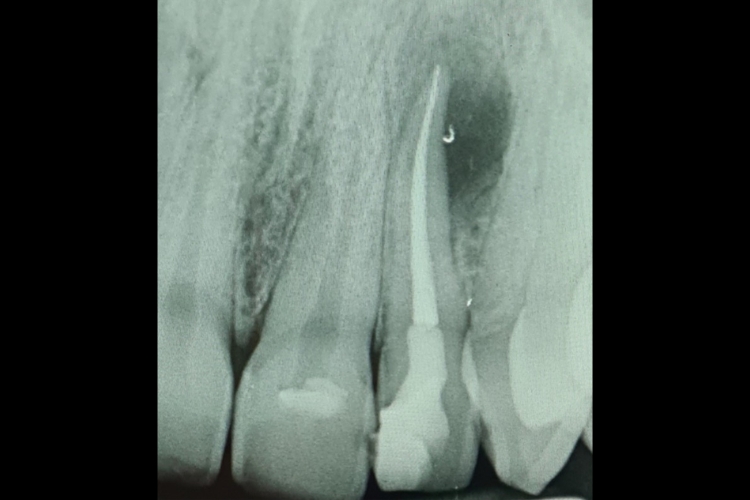

The example above is of a high-quality root canal undertaken by Dr Raj Koner. Root Canal Treatment is an important dental procedure to help relieve toothache and save…